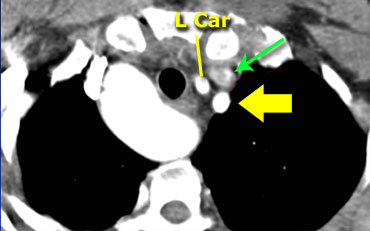

On the left images of a symptomatic child.

On the axial image there is a right arch with the left subclavian artery that comes off on the posterior side and runs behind the trachea and the esophagus.

The compression of the trachea is demonstrated on the volume rendered view.